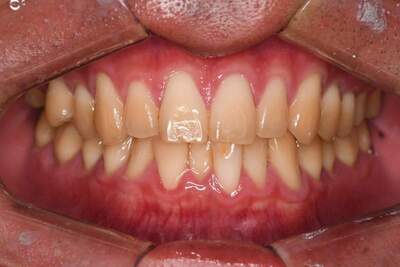

インレー・クラウン・ホワイトニング症例

治療前

治療後

治療期間 11回(4ヶ月)

費用 ・ハイブリッドインレー7本

・ジルコニアクラウン2本

・ホワイトニング:5回

合計:430,500円

治療リスク・副作用 ・詰め物、被せ物をする時は自分の歯を削ることになります

・歯ぎしり・食いしばりが強い方は、セラミックが割れてしまうことがあります。